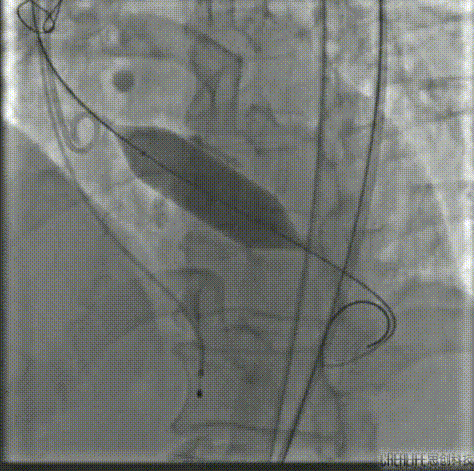

20mm球囊预扩,右无融合处钙化嵴被推开,造影显示无腰征微量造影剂渗漏